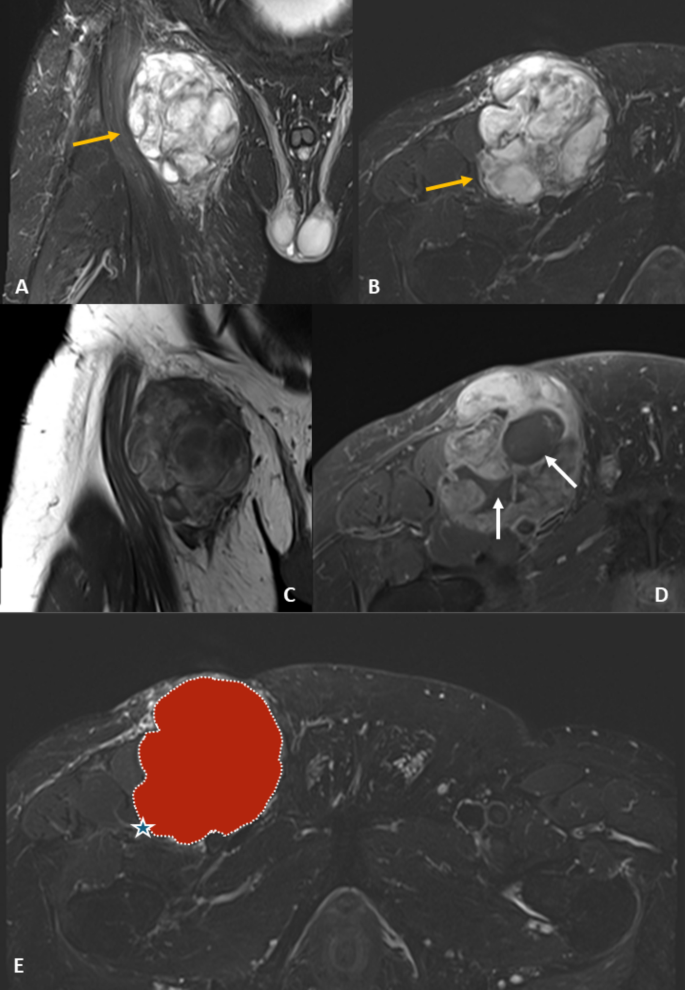

Two segmentation outliers contributed to localized performance dips—one small-volume lesion and one pleural tumor with atypical morphology—where sub-models failed to identify any voxels, resulting in a DSC of 0.0. These rare cases had a disproportionate impact on average fold scores. Notably, other atypical cases, such as an axillary MLPS, were segmented correctly, suggesting generalizability to uncommon localizations. A representative MRI case is shown in Fig. 4, illustrating typical imaging features of MLPS and the accuracy of the manual segmentation mask used for training and model evaluation.

Representative MR images of a 52-year-old man with MLPS in the thigh. (a, b) STIR images show a well-demarcated hyperintense mass with internal septations (yellow arrows). (c) T1-weighted coronal image shows iso-/hyperintensity. (d) Fat-suppressed contrast T1w image reveals heterogeneous enhancement (white arrows). (e) Manual segmentation overlay (red) aligns with tumor margins (star). STIR = short tau inversion recovery; T1w = T1-weighted; FS = fat-suppressed.